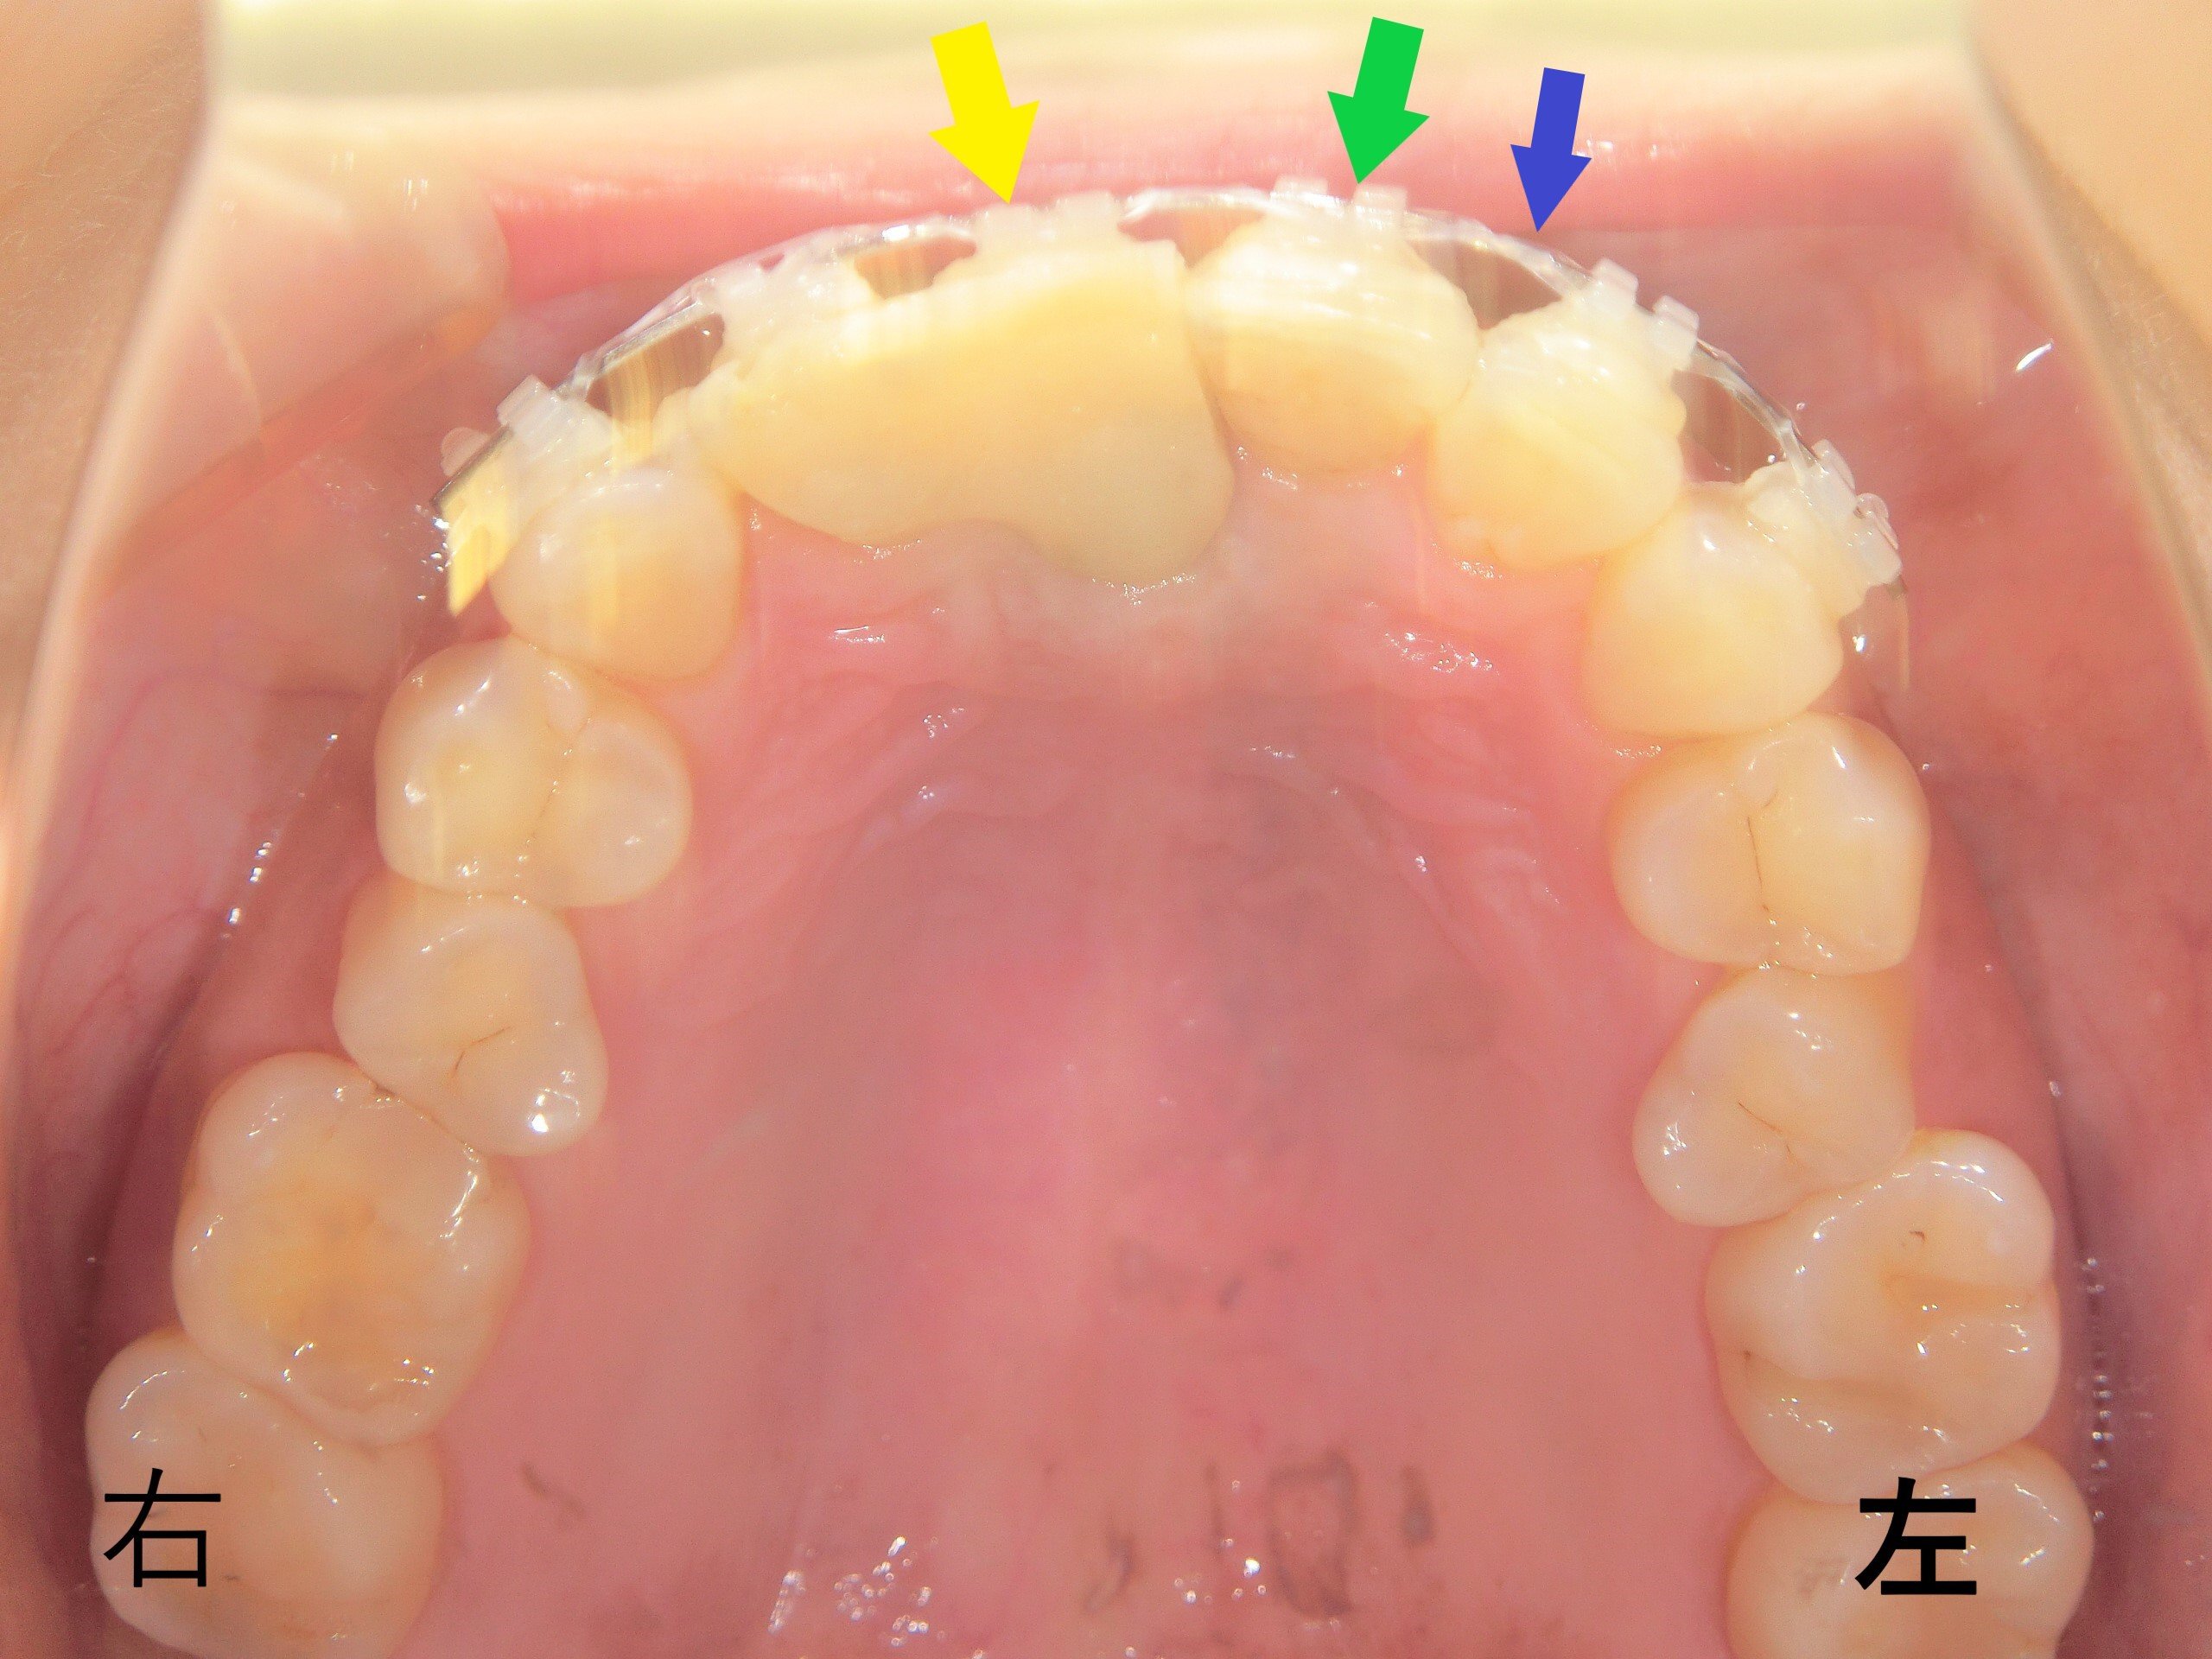

【プチ矯正治療終了後(上顎を下から見た写真)】

治療開始直後の写真と比較すると、左上前歯が右上前歯と同じ位置まで下がっていることが確認できます。